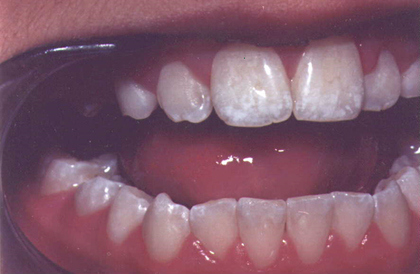

But less about other dangers, for the moment. We want to bring you images of dental fluorosis. They will act as a rough guide to the severity of your condition.

Six types of fluorosis (Source: Fluoride Free, Ireland):

Four pictures of fluorosis (Source: Fluoride: Protected Pollutant or Panacea? Canada):

Five pictures of fluorosis (source: Fluoride Action Network, USA):

Six pictures of fluorosis (source: Provided by Dr Susheela, India):